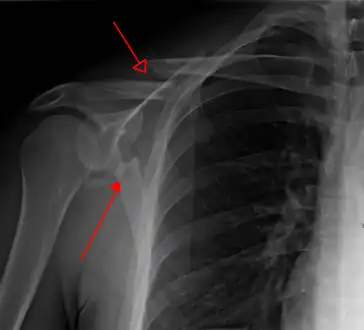

Most fractures of the scapula can be seen on a chest X-ray; however, they may be missed during examination of the film.[1] Serious associated injuries may distract from the scapular injury,[4] and diagnosis is often delayed.[3] Computed tomography may also be used.[1] Scapular fractures can be detected in the standard chest and shoulder radiographs that are given to patients who have had significant physical trauma, but much of the scapula is hidden by the ribs on standard chest X-rays.[4] Therefore, if scapular injury is suspected, more specific images of the scapular area can be taken.[4]